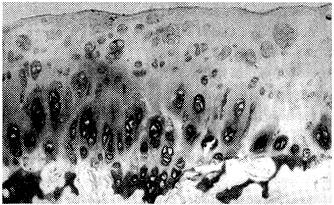

韧带无张力组,光镜下软骨退变较10天时又加重。细胞减少、有核缩、核碎、核溶现象。基质染色不均。韧带有张力组,软骨基质与细胞的改变较10天时也有加重。细胞减少,簇集现象更加明显,软骨表层凹陷不平。见图4。

图4.韧带有张力组:术后15天,软骨细胞排列紊乱,细胞簇集增加,有核溶及细胞坏死现象,基质淡染,软骨表面凹陷不平。甲苯胺兰×100

Fig.4Exp group. MCL in normal tension:15 days after operation,further disorder of chondrocytes arrangement,more cell cluster,cell necrosis,matrix distained,surface was not smooth. Toluidine blue×100